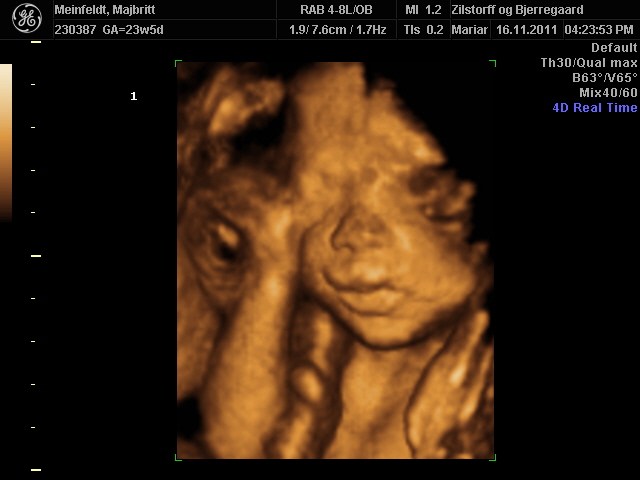

Hvor er det dejligt for jer, at have fået set jeres skønne børn.. Der er bare nogle rigtig fine billeder..

Vi har godt nok valgt ikke at få en 3D skanning, men man bliver helt varm om hjertet når man ser de fine billeder.. Og som der er skrevet længere oppe, der er jo lang tid til marts